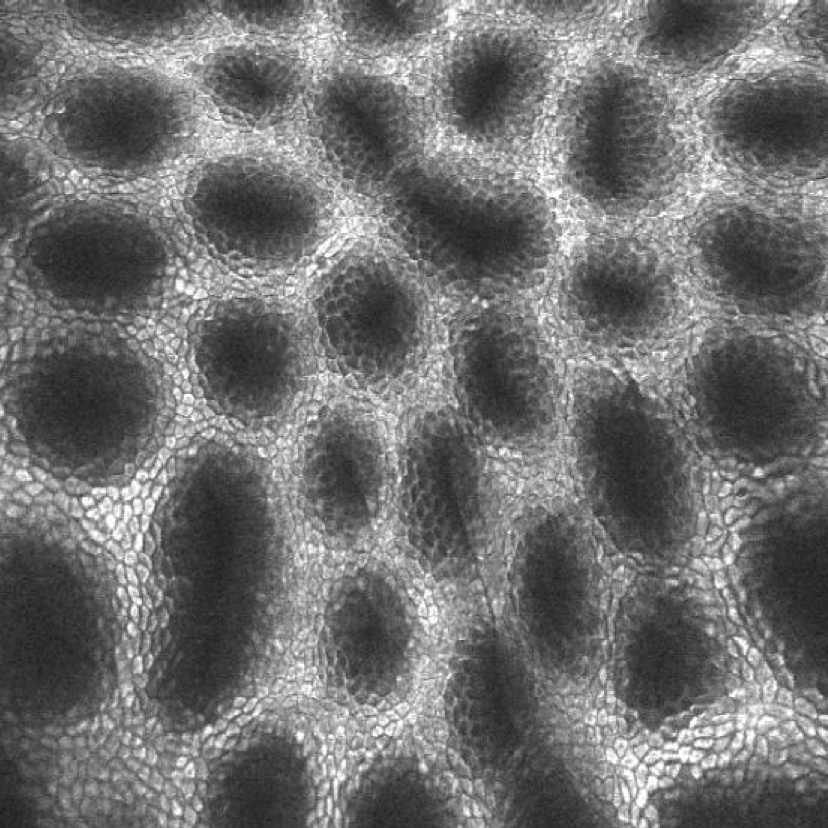

内镜分辨率越高,就能够展现更多的细节,细节对胃肠病的诊断有什么用呢?用处太大了。关注过前面关于早期胃癌诊断方面文章的朋友,应该已经知道:做胃镜的一个重要意义是发现还没有症状的早期胃癌。而早期胃癌相对进展期的胃癌,面积更小,表面和周围正常粘膜基本平行,既不明显隆起也不明显凹陷。但是如果仔细看,就会发现这个地方和周围不太一样。怎么不一样?是胃小凹不一样。从胃镜下看,胃粘膜是非常光滑的,但放大了看,或者分辨率足够高的时候,就会发现其实一点也不光滑,有很多规则排列的凹陷的小孔,或者突起的像鹅卵石一样的结构,这就是正常的胃小凹。而早期胃癌的胃小凹因为癌细胞的侵犯,胃小凹变得很不规则,甚至完全消失。如果用老式的胃镜,分辨率比较低,就可能发现不了这样细微的变化。而新式的高分辨率的胃镜,再配上一个大的显示屏,胃小凹分毫毕现。这样的变化自然更容易发现。第一次用高分辨率内镜的感觉,就像我第一次看高清压制的《王者归来》,居然发现每个兽兵脖子上都系着一条恶心的领巾,之前看过多次普通DVD压制的都没有注意。

进入21世纪之后,内镜技术第一次使用了激光作为射入光源。其实这也不算什么新东西,只不过把一种实验室里常用的显微镜,叫做激光共聚焦显微镜微型化以后和内镜整合在了一起。为什么要用激光?我们需要先了解激光的特性。第一,激光相比普通光,可以更加精确的到达投射部位,而很少有发散。第二,激光的光谱的频率更加单一,一次激发的激光色更纯,可以获得更小的像素点。依靠第一个特性,可以对观察的粘膜组织进行逐层的扫描,扫描的厚度可以达到仅有几个微米。这样做有什么意义呢?意义和病理检查一定要做切片一样。因为人体组织不透明,所以成块看只能看到表面,要分析内部,切成一个个薄片,达到可以透光的程度,把立体的组织转换成二维图像,就可以观察了。而依靠第二个特性,可以把分辨率提高到更高的高度。放大内镜只能放到到一百多倍,再放大就会出现马赛克,而共聚焦显微内镜则最大可以放大五百到一千倍,这已经达到甚至超过了普通显微镜检查的放大倍数了。别说胃小凹,连细胞、微血管都可以清晰显示。现有的高速扫描的探头式共聚焦显微内镜,甚至可以显示红细胞在微血管里滚动的动态视频。这以前只在科教片里看过。尽管大家对共聚焦显微内镜在临床上究竟能够起到多大作用还有疑问,但这无疑是当前光学技术在内镜检查中展现的极致了。

共聚焦激光显微内镜